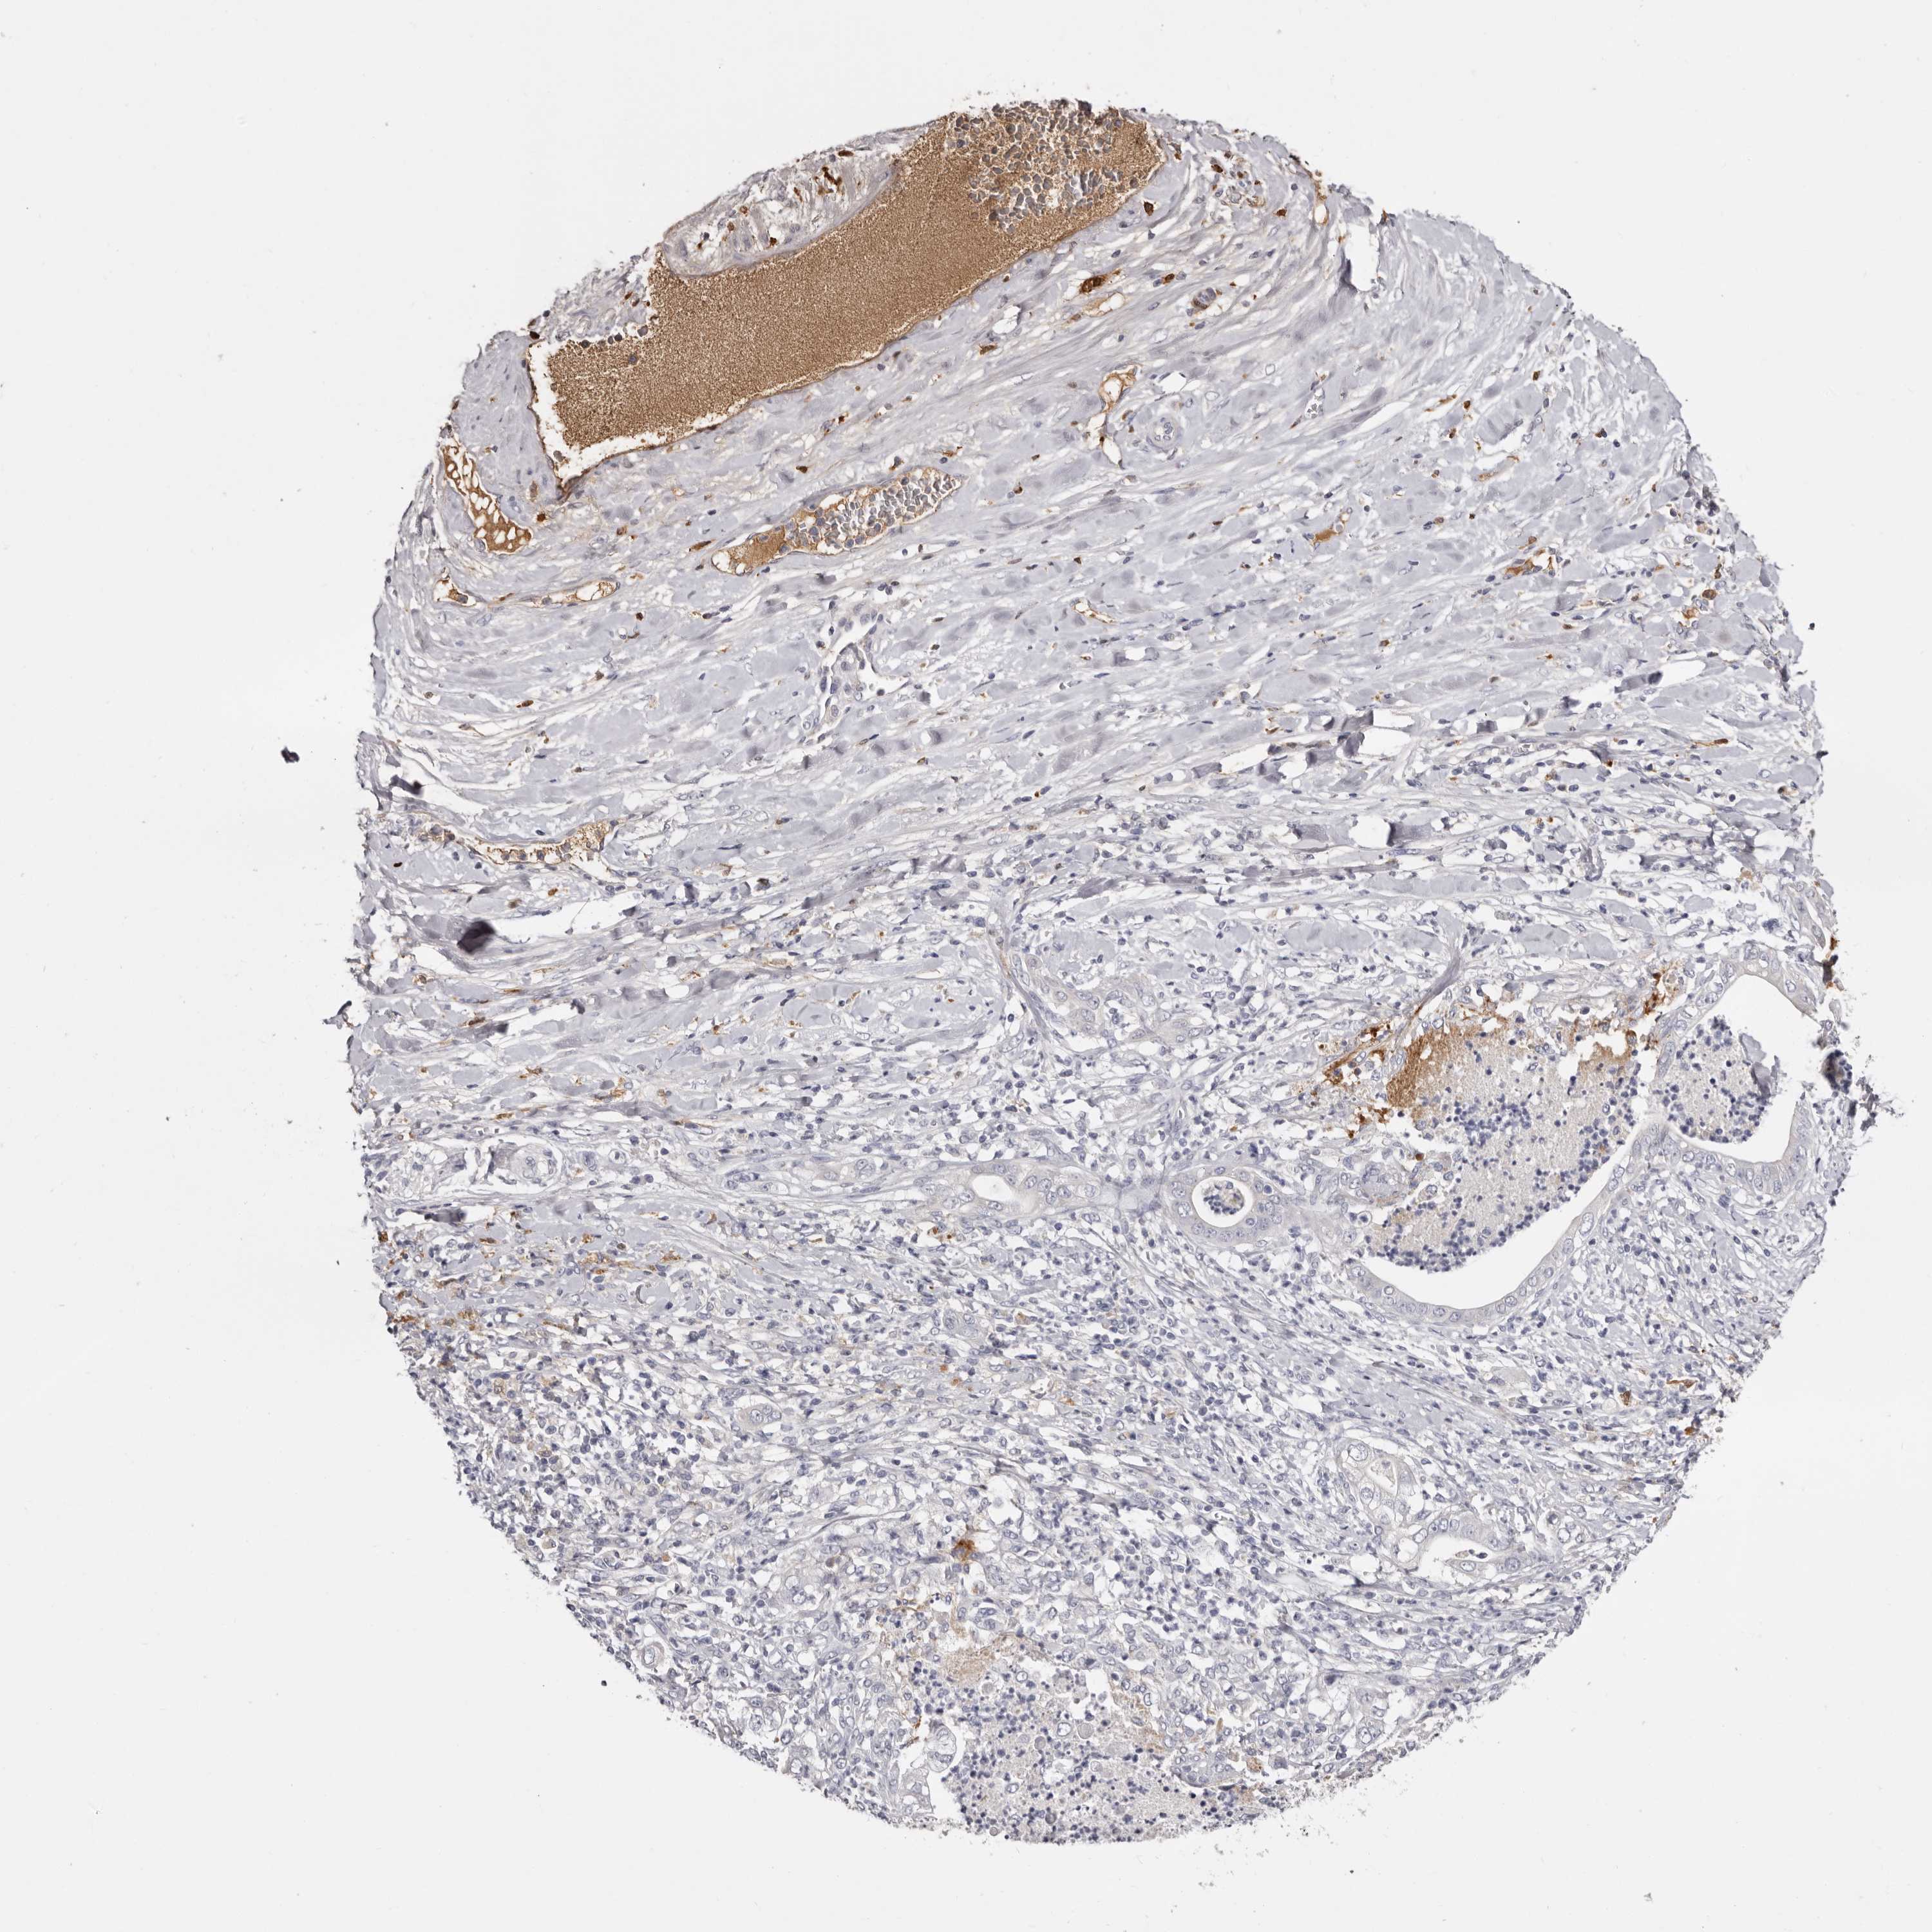

PANCREATIC CANCER - Protein expressioni

A mouse-over function shows sample information and annotation data. Click on an image to view it in a full screen mode. Samples can be filtered based on level of antibody staining by selecting one or several of the following categories: high, medium, low and not detected. The assay and annotation is described here.

Note that samples used for immunohistochemistry by the Human Protein Atlas do not correspond to samples in the TCGA dataset.

Antibody stainingi

Antibody staining in the annotated cell types in the current human tissue is reported as not detected, low, medium, or high, based on conventional immunohistochemistry profiling in selected tissues. This score is based on the combination of the staining intensity and fraction of stained cells.

Each image is clickable and will lead to virtual microscopy that enables deeper exploration of all samples and also displays staining intensity scores, fraction scores and subcellular localization as well as patient and tissue information for each sample.

Antibody HPA024770

Antibody HPA027115

Staining

High

Medium

Low

Not detected

Intensity

Strong

Moderate

Weak

Negative

Quantity

>75%

75%-25%

<25%

None

Location

Nuclear

Cytoplasmic/membranous

Cytoplasmic/membranous,nuclear

Adenocarcinoma, NOS